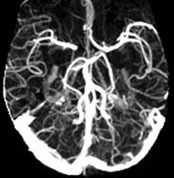

• Angiograms – A scan that uses X-rays, computed tomography angiography (CTA) or magnetic resonance angiography (MRA) to show the blood flow through the arteries or veins.

• Magnetic Resonance Angiography (MRA) – A special kind of MRI that examines blood vessels.